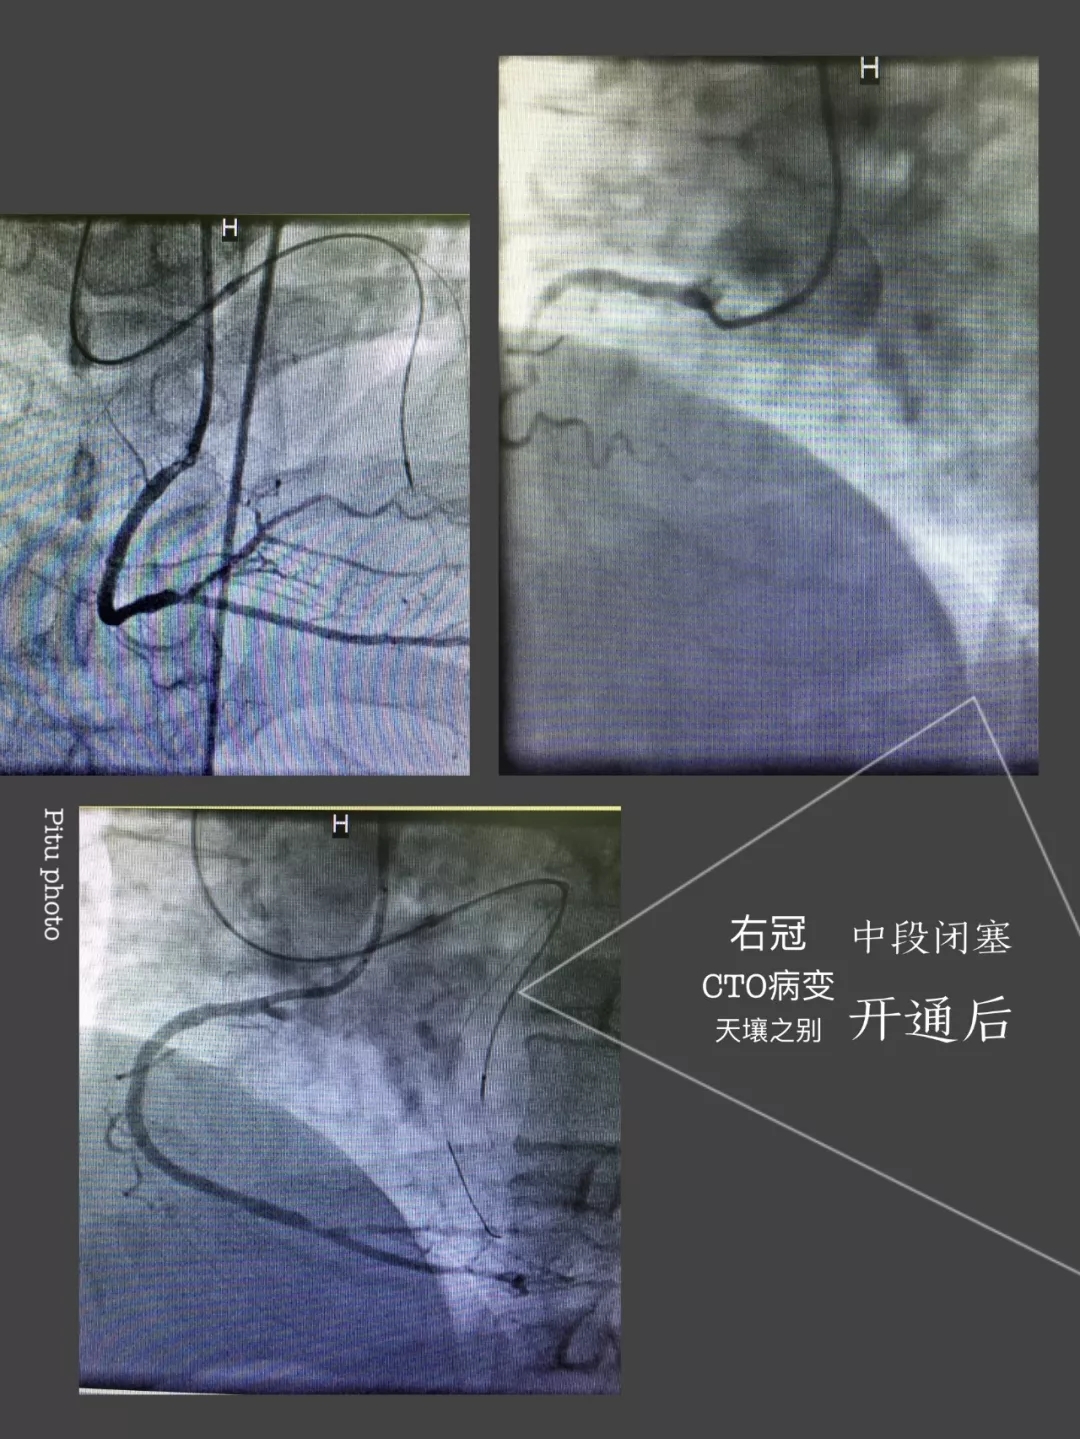

心内三完成21点游戏攻略站 首例逆向开通冠脉CTO病变